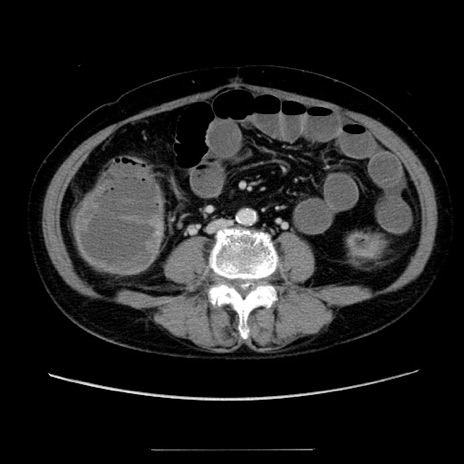

症例5(横断像)

【症例】70歳代女性

【主訴】お腹が張る

【現病歴】1週間くらい前から腹部膨満の自覚あり。昨日夜から増悪したため、本日救急外来受診。

【身体所見】意識清明、BT 36.5℃、BP 165/106mmHg、HR 80bpm、SpO2 98%、腹部:膨満、軟、自発痛・圧痛なし、触診にて不快感あり、腸蠕動音:減弱

【データ】WBC 12600、CRP 1.04